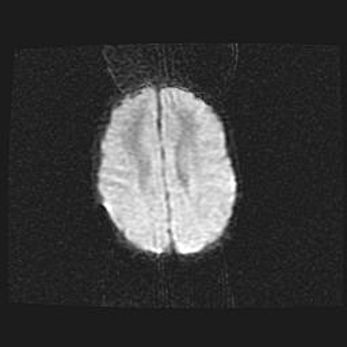

Церебральная ишемия II.

Возраст: 5 дней

Вес: 3400 г

Пол: женский

Окружность головы: 35 см

Срок гестации: 39 недель

Церебральная ишемия – это заболевание, характеризующееся недостаточностью (гипоксией) либо полным прекращением (аноксией) снабжения мозга кислородом по причине закупорки одного или нескольких сосудов. Это приводит к  что метаболическим расстройствам различной степени тяжести в тканях головного мозга, развитию коагуляционных некрозов и гибели нейронов.